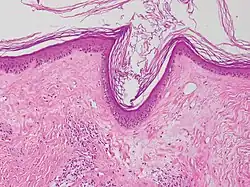

| Lichen sclerosus | Hyperkeratosis, atrophic epidermis, sclerosis of dermis and dermal lymphocytes.[3] |